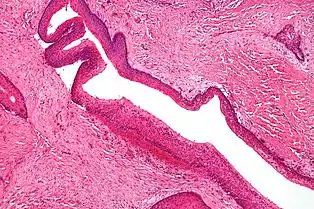

سرطان رودهٔ بزرگ نا-پولیپوزیس ارثی (HNPCC) که بانام نشانگان لینچ نیز شناخته میشود، یک نشانگان سرطان غالب آتوزومی است که خطر سرطان روده بزرگ – مقعدی را افزایش میدهد. این سرطان با جهشهایی ژنی در تعمیر ناجور DNAیا MMR رخ میدهد، ژنهای شایان توجه MLH1، MSH2، MSH6 و PMS2 هستند. افزون بر سرطان رودهٔ بزرگ – مقعدی، فراوانی بسیاری سرطانهای دیگر نیز افزایش مییابد. آنها عبارت اند از: سرطان اندوتلیال، سرطان معده، سرطان تخمدان، سرطانهای رودهٔ کوچک و سرطان لوزالمعده. همچنین HNPCC با یک هجوم آغازین سرطان رودهٔ بزرگ – مقعدی همراه شدهاست. ژنهای MMR در تعمیر DNA هنگامی که بازها بر روی هر رشته از DNA جور نشود، درگیر میشوند. ژنهای MMR معیوب اجازه الحاق ممتد و جهشهای حذف در مناطقی از DNA که با عنوان ریزماهوارهها[برابرها 56] شناخته میشود را میدهد. این توالیهای کوتاه تکراری DNA ناپایدار گشته، منجر به یک حالت نااستواری ریزماهواره[برابرها 57] میشود. ریزماهوارههای جهشیافته معمولاً در ژنهای درگیر در راهاندازی و پیشرفت تومور یافت میشوند و MSI میتواند ابقای زیستی یاختهها را بالا برده و منجر به سرطان گردد،[4][20]،[21][22]